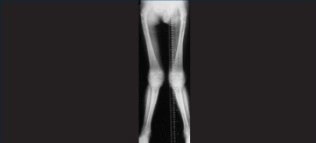

Mucopolysaccharidosis type I musculoskeletal manifestations

Adults are often stocky in build, their trunks shorter than their limbs, and their necks may be short and stiff.4,9 Bone abnormalities are common in those with MPS I, including:

- Hip deformations15

- Ovoid vertebrae15

- Widening of the ribs.15

- Poorly formed pelvis7,15

- Gibbus deformity of the back7,15

- Shortened phalanges of the hands7,15

- Joint contractures7,16

Skeletal dysplasia can occur in the severe types of MPS I but is frequently missing or subclinical in patients with attenuated MPS I.15

Joint stiffness, pain and contractures are common among patients with attenuated MPS I.7 Evolving joint pain and joint contractures in the absence of inflammation should always raise suspicion of an MPS disorder.16

Limited range of motion mobility in the absence of inflammation should raise suspicion of MPS I.